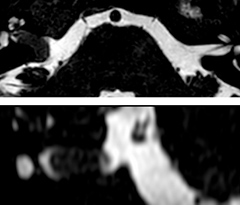

In this example, the optional 3D multishot susceptibility weighted sequence with 0.6 mm isotropic voxels is 2 lesions with a central vein sign (arrows) and one lesion with a phase-rim sign (arrowhead). The total scan time, including SmartBrain and axial PD/T2 3mm, is 11:10 min. and is 18:30 min. with the optional 3D PSIR and 3D SWI multishot included.

“We used to have long examination times for certain types of patients, a few lasting more than 40 minutes,” says Dr. Savatovsky. “What is remarkable, is that now all these examinations are below 30 minutes, which opens up opportunity to add more sequences when needed. It’s really hard to keep a patient for more than 40 minutes in the scanner, but because we have now cut scan times by at least 10 minutes, we can add more sequences without making the exam too long. And this is where the new system helps us make a difference. Examples include our examinations for informing brain tumor classification or giant cell arteritis workup, or for intracranial wall imaging – so in patients where we need several advanced sequences or high resolution sequences.” “We added three additional sequences in our brain neoplasm classification exam: a 3D SWI sequence, APT and ASL on top of 3D morphologic sequences, an isotropic DSC (dynamic susceptibility contrast) and multivoxel spectroscopy. I think that in patients that need a classification for brain mass, for example, we can provide a more detailed and confident diagnosis than before, allowing the clinicians to decide for either a medical workup if no tumor is suspected, or for neurosurgery as soon as possible if a neoplasm is suspected.” “In multiple sclerosis patients, we increasingly include a multishot susceptibility sequence [3] in our routine cases, thanks to the shorter scan times. Our abbreviated MS protocol for brain is around 8 to 9 minutes, so we can ask for one or two additional sequences to visualize the central veins, or to get an additional contrast to better depict posterior fossa lesions. In cases of white matter lesions of unknown significance on FLAIR images, for example when we see high signal hyperintensities in the brain, we can add on more advanced sequences such as PSIR (phase sensitive inversion recovery) or susceptibility-weighted sequences to help us in distinguishing between MS and nonspecific or vascular abnormalities in these inflammatory cases.”